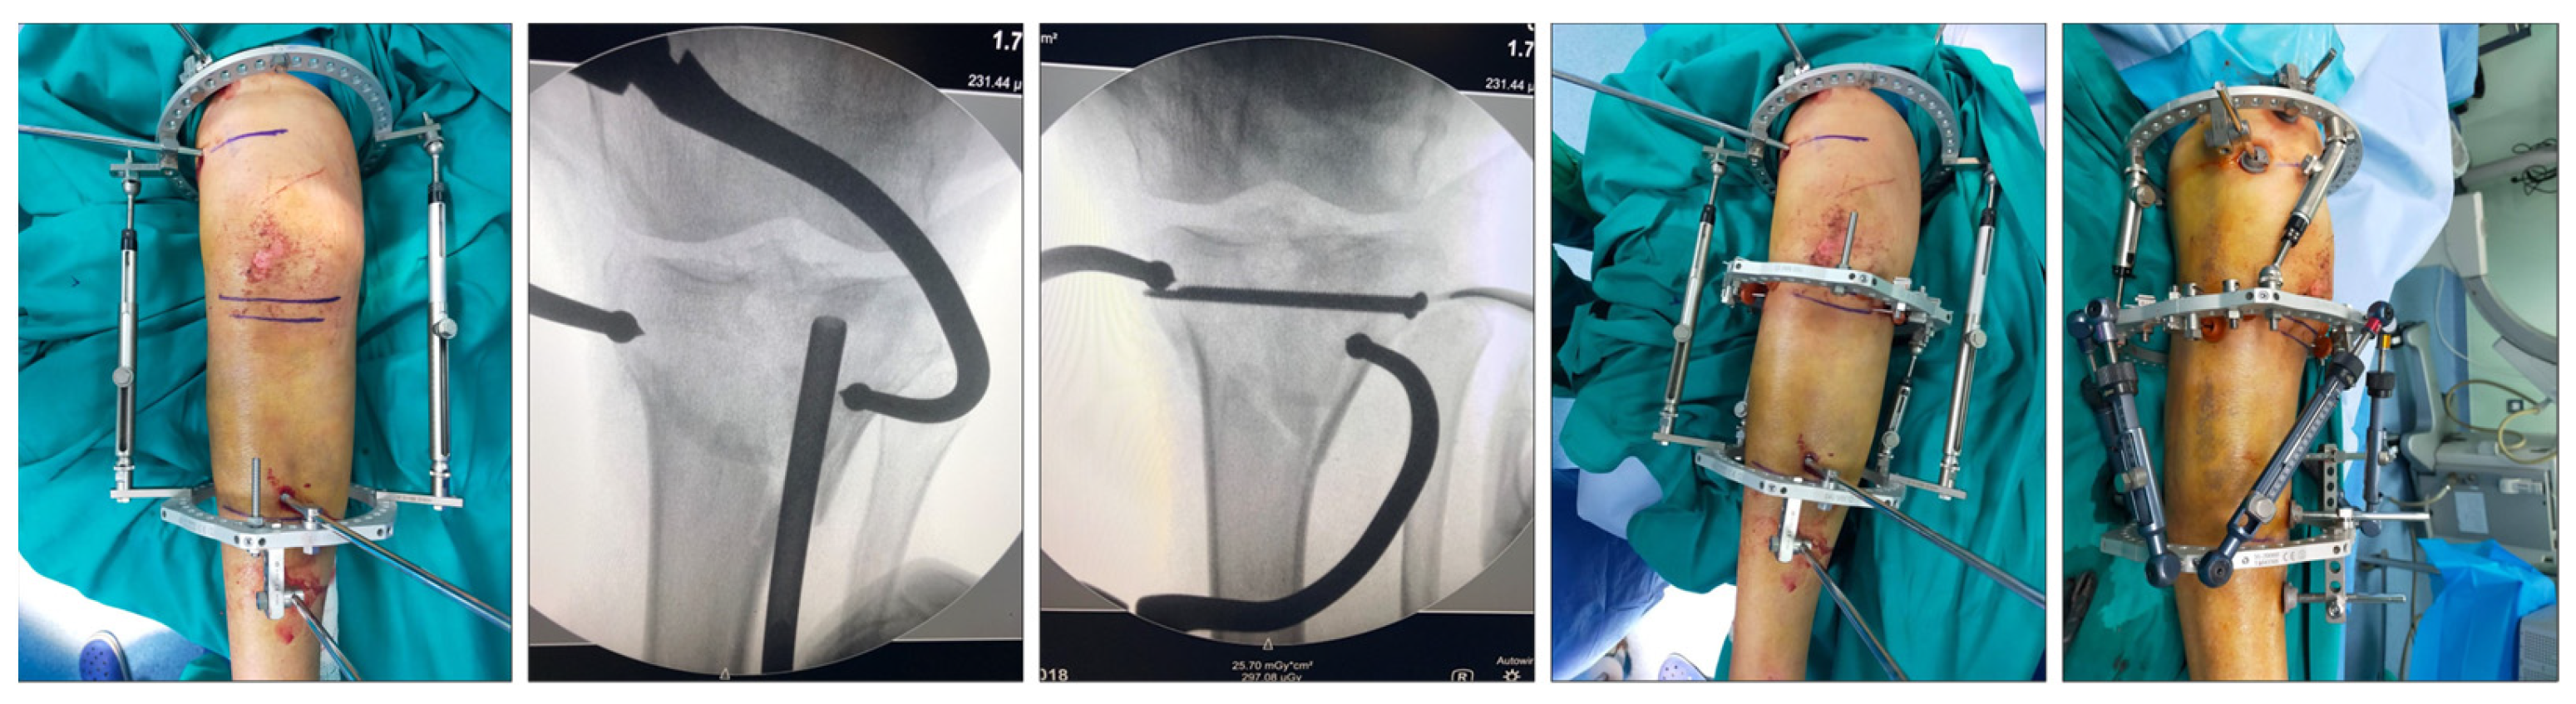

Figure 1 shows a schematic representation of the fracture reduction and fixation technique used in this series. Figure 2 shows a real case.

Figure 2.

Fracture reduction and fixation in a real patient.